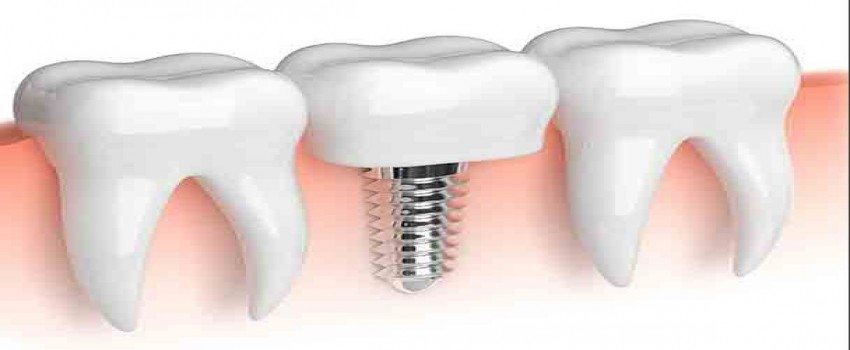

ایمپلنت دندان: عواقب طبیعی از دست دادن دندان های آسیاب ماگزیلاری، از دست رفتن ارتفاع استخوان تاج است. وقتی دندان ها برداشته می شوند، ریج های باقی مانده می توانند در عرض 3 سال اول 30 تا 60 درصد ارتفاع و عرض خود را از دست بدهند. حفره ی فک می تواند هوا بگیرد و بزرگتر شود و این باعث می شود که ارتفاع ریج استخوانی باقی مانده کاهش یابد.

هنگامی که بین تاج و کف سینوس فاصله عمودی ایجاد می شود، امکان قرار دادن ایمپلنت های دندانی می تواند به خطر بیفتد. هنگامی که استخوان کافی برای ثبات و حمایت طولانی مدت از ایمپلنت دندان و بازسازی آن وجود ندارد، روش برداشت سینوس اجرا می شود.

ایمپلنت ماکرو 6.0 میلیمتر (OCO Biomedical) یک جایگزین مناسب برای ریج هایی است که ارتفاع عمودی استخوان آن به خطر افتاده است. این موضوع پیچیده است، که اجازه جاگذاری در استخوان نرم و سخت با پایداری اولیه ی عالی را می دهد، دارای تعویض پلت فرم است، و پروتکل جاگذاری ساده ای دارد.